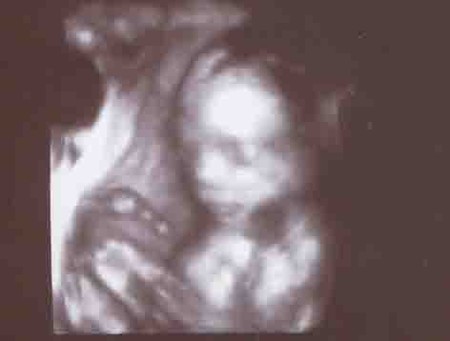

кровиночка...

Василиса Кирилловна... мы тебя любим и ждем...